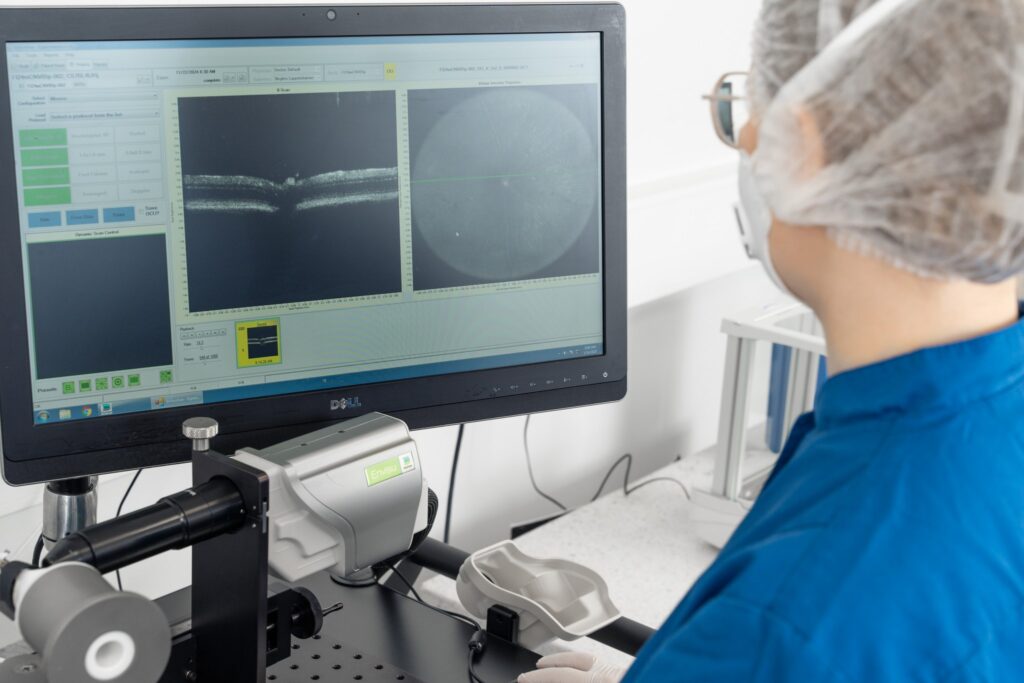

Retinal morphology is monitored utilizing spectral-domain optical coherence tomography (SD-OCT), while visual function is evaluated using flash electroretinography (fERG) and optomotor response (OMR). These non-invasive techniques enable comprehensive monitoring of disease progression with longer follow-up periods. Additionally, we provide histology and immunohistochemical stainings, enabling detailed analysis of tissue morphology and molecular markers to assess disease progression and treatment efficacy.

Efficient model follow-up non-invasively utilizing our latest state-of-the-art technologies.

Experimentica offers extensive in vivo imaging capabilities for high-resolution ocular assessments across species.